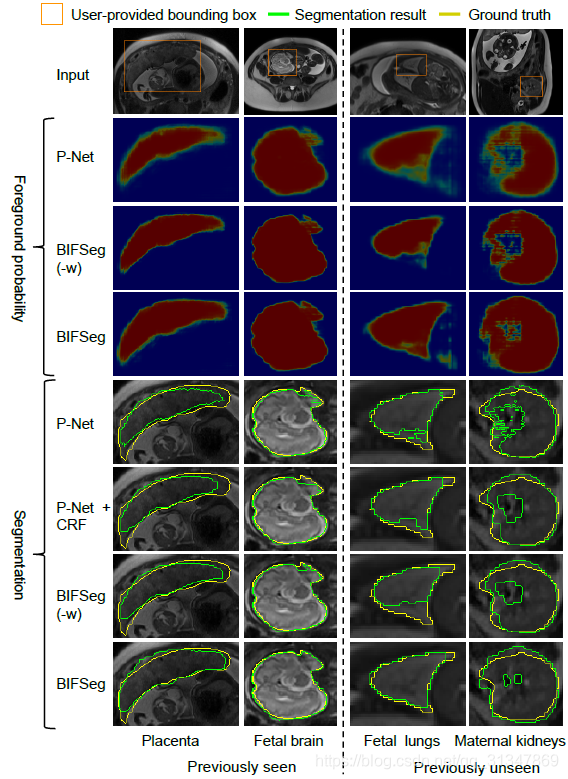

(2)Unsupervised Image-specific Fine-tuning:

对于无监督的微调,P-Net 获得的初始分割结果分别经过 CRF、BIFSeg(-w) 和 BIFSeg 进行调整,结果如下:

第 2 行为 P-Net 获得的初始前景概率图,红色区域周边存在很多概率接近 0.5 的像素点,说明初始分割结果有很高的不确定性。

第 3、4 行分别为经过 BIFSeg(-w) 和 BIFSeg 调整后的前景概率图

接下来就分别是 P-Net、P-Net+CRF、BIFSeg(-w) 和 BIFSeg 的分割结果。

虽然后面三个都是对 P-Net 初始分割结果的调整,但是明显 BIFSeg 的调整结果是最好的。